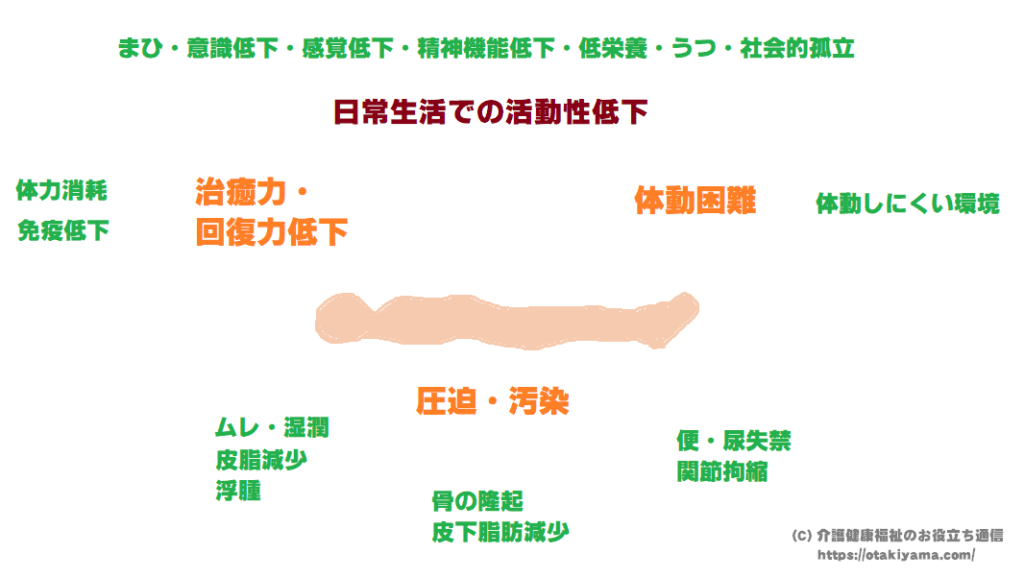

褥瘡の原因・好発部位・進行度分類・褥瘡予防や対策の記録方法介護健康福祉のお役立ち通信。

褥瘡 じょくそう 病気の知識介護の知識訪問看護・24時間の在宅看護等のサービスを自費で! ナースアテンダント。

実践します!褥瘡ケア「いつもの方法を見直してみよう」エール在宅診療所。

褥瘡の予防と観察ポイント見て!わかる!病態生理と看護 花子のまとめノート。